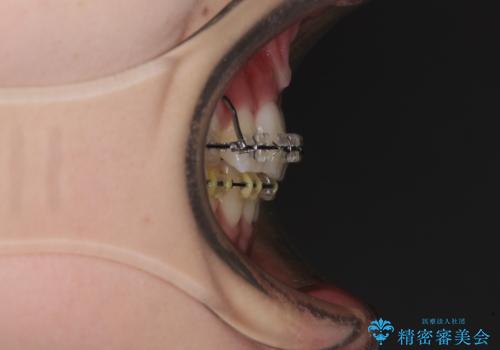

治療途中で転院 抜歯矯正の仕上げ治療

- 地元で抜歯治療を行っている途中、東京へ転職したため治療を継続して欲しいとのことで来院された患者様です。

出っ歯を抜歯矯正にて治療をしていらっしゃいましたが、抜歯スペースが少し残っていたため、閉じて歯列を仕上げていくこととしました。